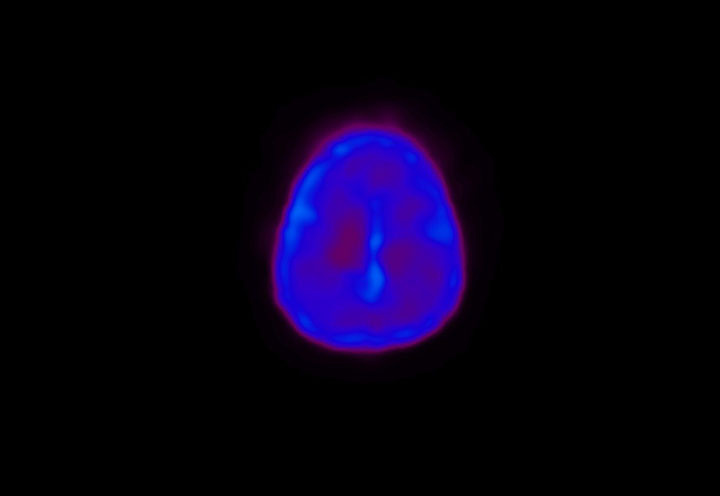

Head / Case4 : Amyloid

Sagittal

Courtesy : Kindai University Hospital

- Imaging protocol

- Injected dose: 3.21 MBq/kg, 18F-Flutemetamol

- Uptake time: 100 minutes

- Scan time: 20 minutes